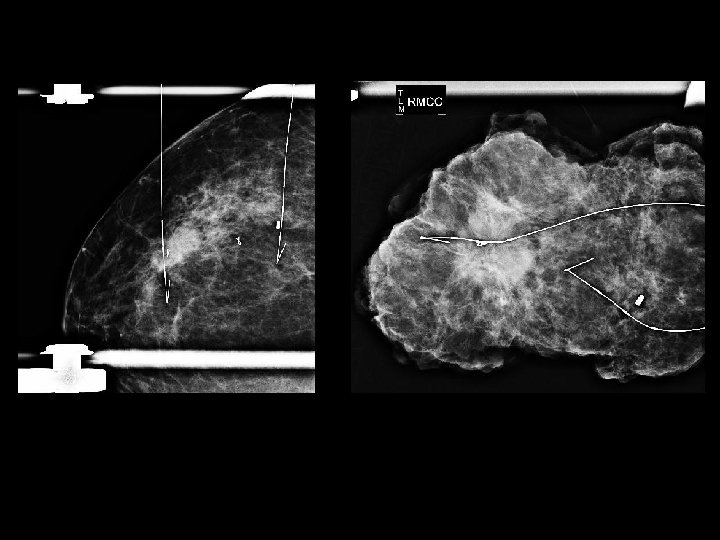

Image Samples

MIP